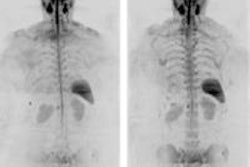

The authors retrospectively reviewed 300 multiple myeloma cases, spanning 13 years, in which patients were diagnosed using both RSS and PET/CT; only the low-dose CT component of PET/CT was used for comparison.

Two radiologists working independently assessed lytic lesions in the skull, spine, sternum, flat bones, and proximal long bones in scans acquired with both modalities in 51 patients (mean age, 56 years).

Whole-body CT found 968 lesions versus 248 for RSS (p < 0.001) in 42 patients, 39 of whom had more lesions at CT than at skeletal survey. Eight cases with lesions at CT would have been missed.